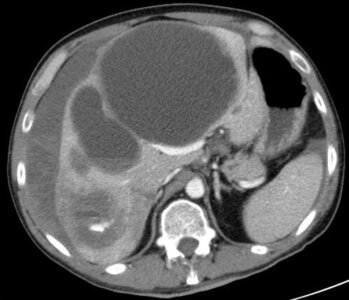

CT des Oberbauchs: Multiple zystische Lebermetastasen eines Klarzellsarkoms mit aktiver Blutung im Segment 6. Mehrere Blut-Flüssigkeitsspiegel in den zystischen Metastasen und subkapsulär.